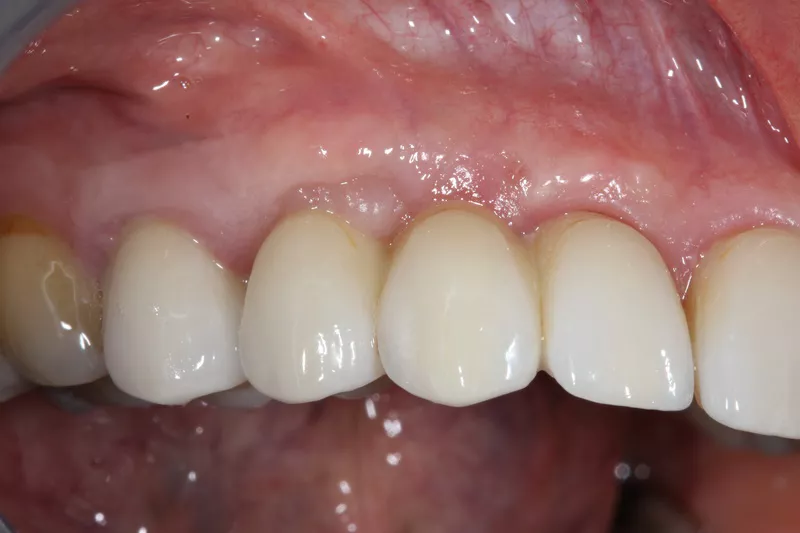

16a-b. Final situation after inserting bridges to 15 Ncm, cementing the crown to tooth 15, and gluing the veneers to teeth 11 and 21.

16c. 4 years post implant placement.

18. Situation 4 years post implant placement.